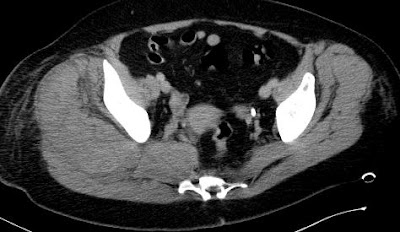

A beteg felvételére DIC miatt került sor, a háttérben AML igazolódott.

A jobb oldali crista biopsia után a csípőtájék fájdalmassá vált, a beteg a jobb lábát emelni nem tudta, haematocrit esett.

Nagy kiterjedésű, coronalis síkban 20 cm-es, az incisura ischiadica maioron beterjedő (valószínűleg a n. ischiadicust comprimáló) haematoma látszik.

2011.01.14. CT